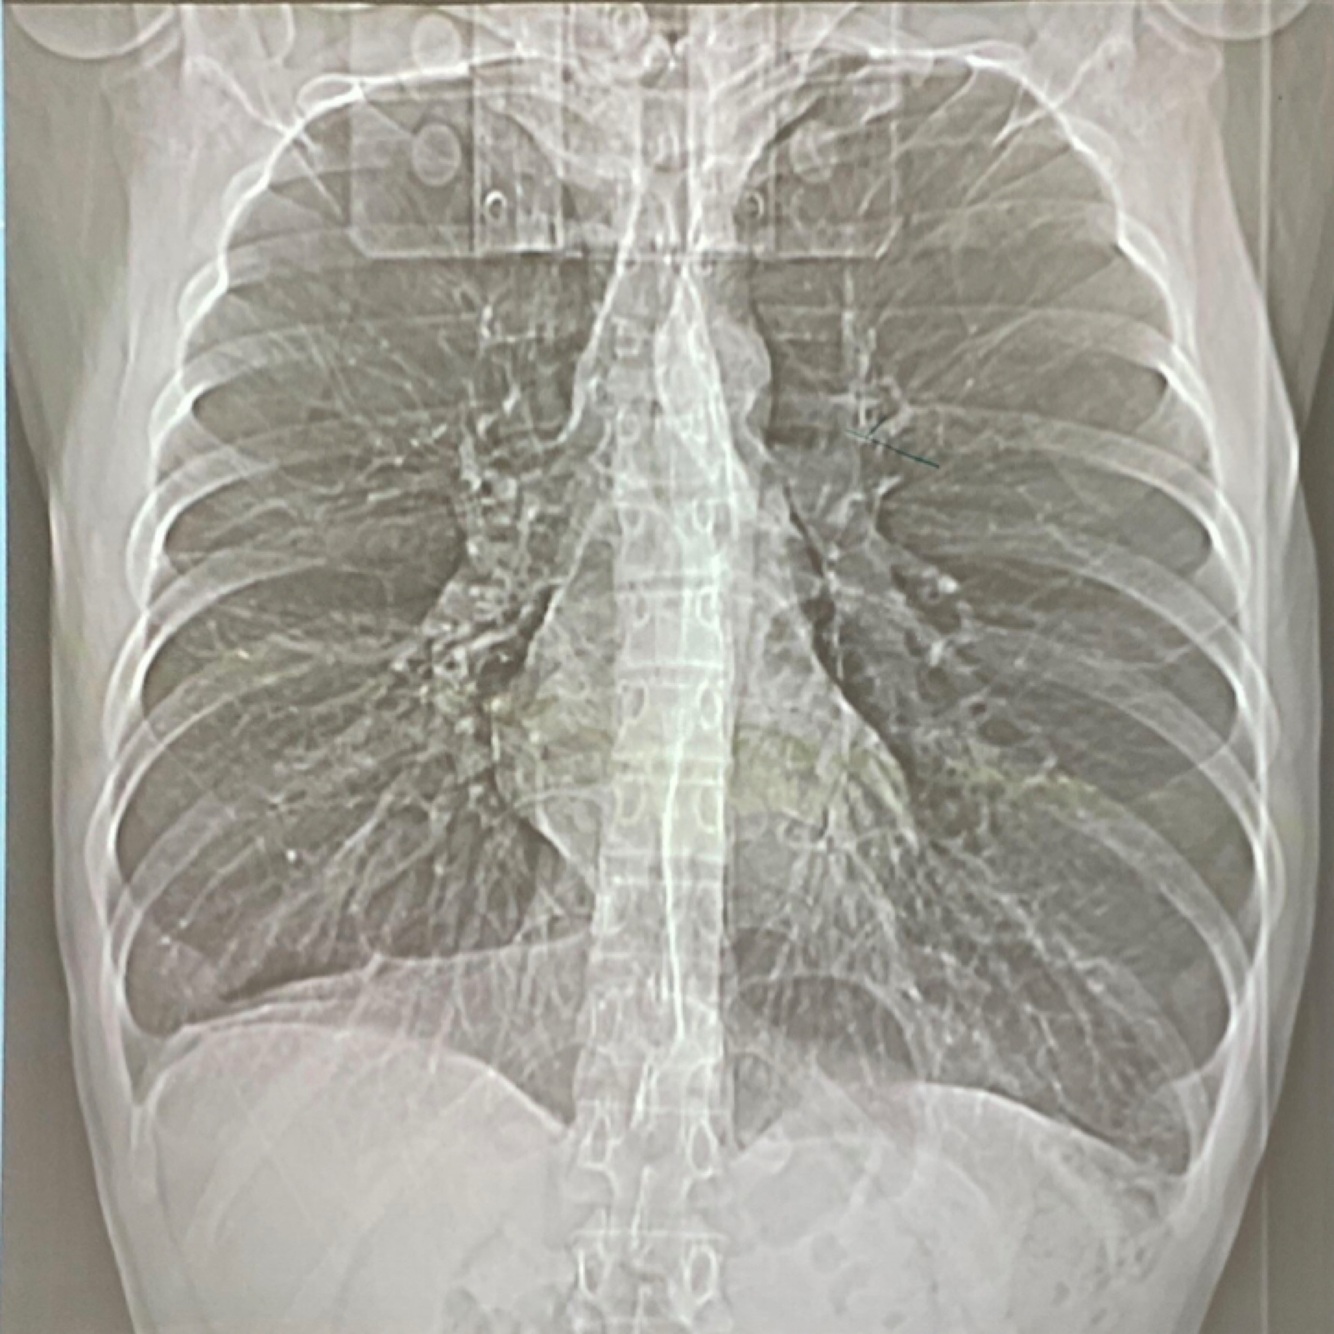

¿Cómo encontraremos una Rx de Tórax en px con EPOC?

A

-Volumen pulmonar aumentado

-Diafragmas planos y abatidos

-Silueta cardiaca alargada

-Aumento de espacio retroesternal

-Márgenes broncovasculares visibles

¿Cómo veremos una Rx en un enfisema predominante?

-Hiperclaridad difusa

-Disminución de las marcas vasculares

-Aumento de diámetros del tórax

-Aplanamiento del diafragma

-Ampliación y horizontalización de arcos costales